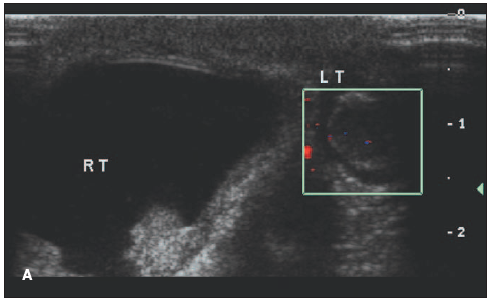

A baby boy born via normal spontaneous vaginal delivery to a 26-year-old gravida 4, para 1 was brought for routine 2-week hospital follow-up.